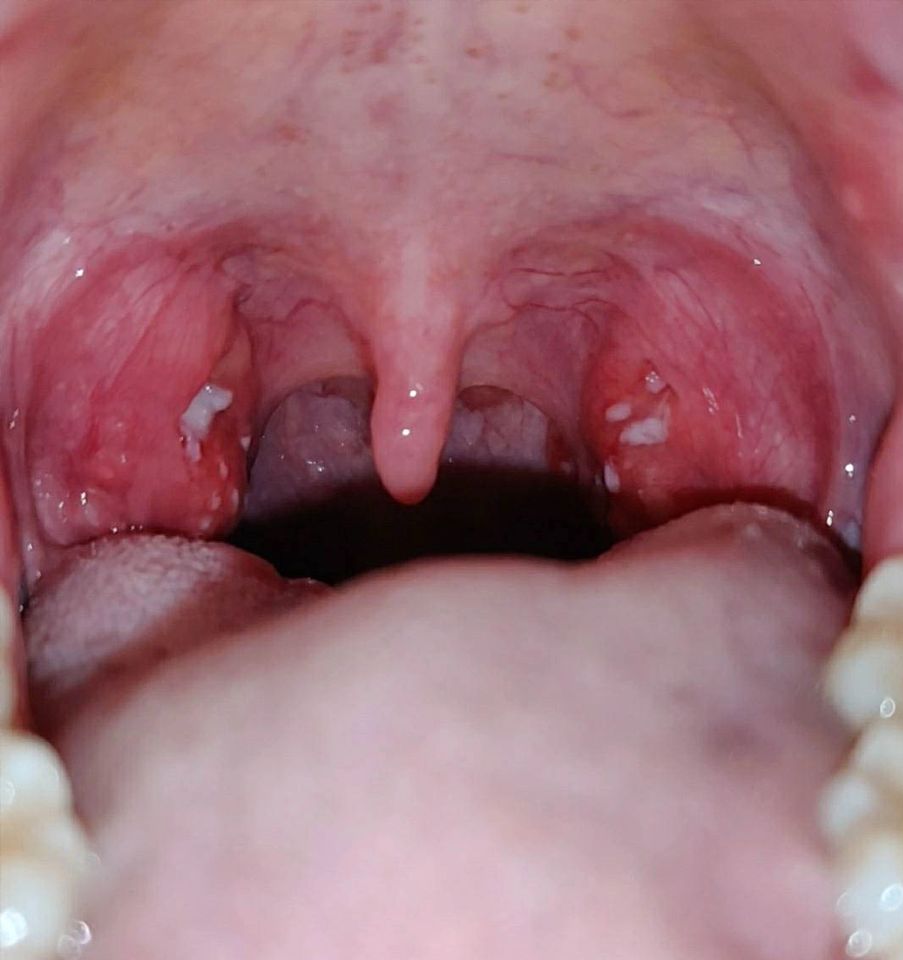

Φωτογραφίες πραγματικών περιστατικών από το εξεταστήριό μας

Στο ιατρείο του Τσιλιώνη Απόστολου, στην πόλη του Βόλου, πραγματοποιούνται εξετάσεις ΩΡΛ με προηγμένα ιατροτεχνολογικά μέσα για τη διενέργεια ελέγχου σε ποικίλους τομείς της Ωτορινολαρυγγολογίας και της Χειρουργικής.

- Εξέταση στοματικής κοιλότητας, φάρυγγα και λάρυγγα